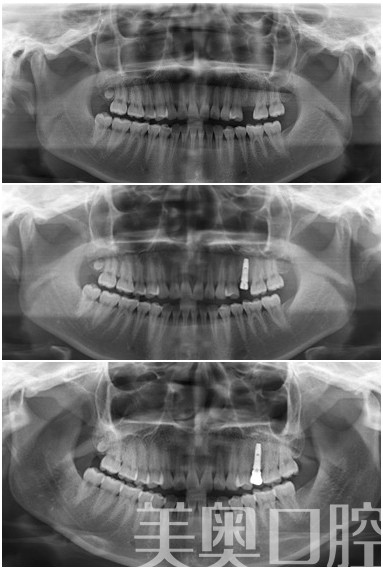

美奥(苏州)5S即刻种植牙

患者感受:我种牙很顺利的,种时一点也不痛,后来挂了一次水防止发炎,但实际上没有问题。恢复得也好。不是种植问题。现在美奥口腔还是会定期给我联系,咨询牙齿的使用情况以及如何保护,这点我很满意。

美奥点评:奥齿泰种植牙是比较经济的一款种植牙系统,价格容易接受,但是瓷睿刻技术是一种即刻修复技术,造价比较昂贵,对于时间充裕的患者,可以选择普通的全瓷冠来修复。